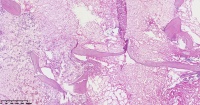

请教老师们这些巨细胞有什么临床意义?

性别

女

年龄

61岁

临床诊断

股骨头骨折

一般病史

标本名称

股骨头组织

大体所见

股骨头骨折处组织

多核吞噬细胞,有纤维素性坏死

是一种反应性改变。